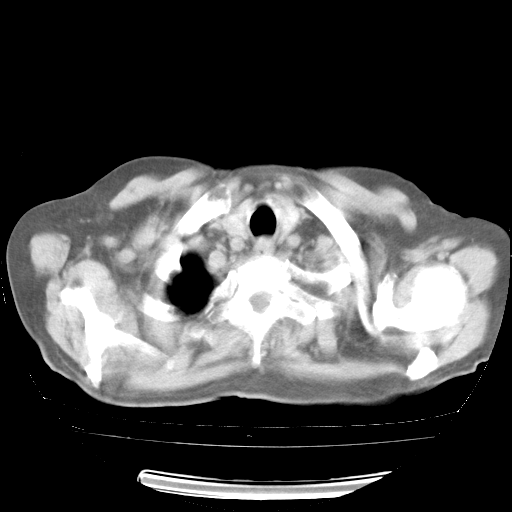

4月28日肺部CT——再次出现类似去年5月9日——透光度降低,“间质性”改变。

4月28日肺部CT——再次出现类似去年5月9日——磨玻璃样、间有“粟粒样”改变。

4月28日肺部CT